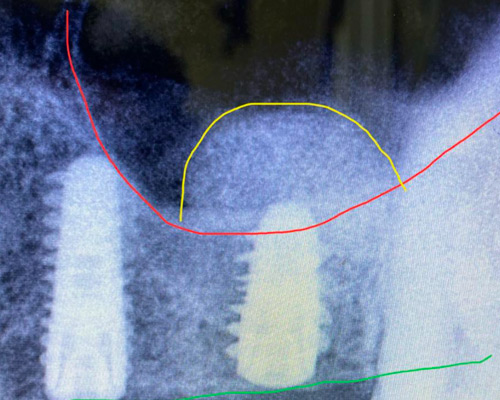

* Dr. Mongalo will review all Ct-scans and 3D images of surgical patients operated on daily.